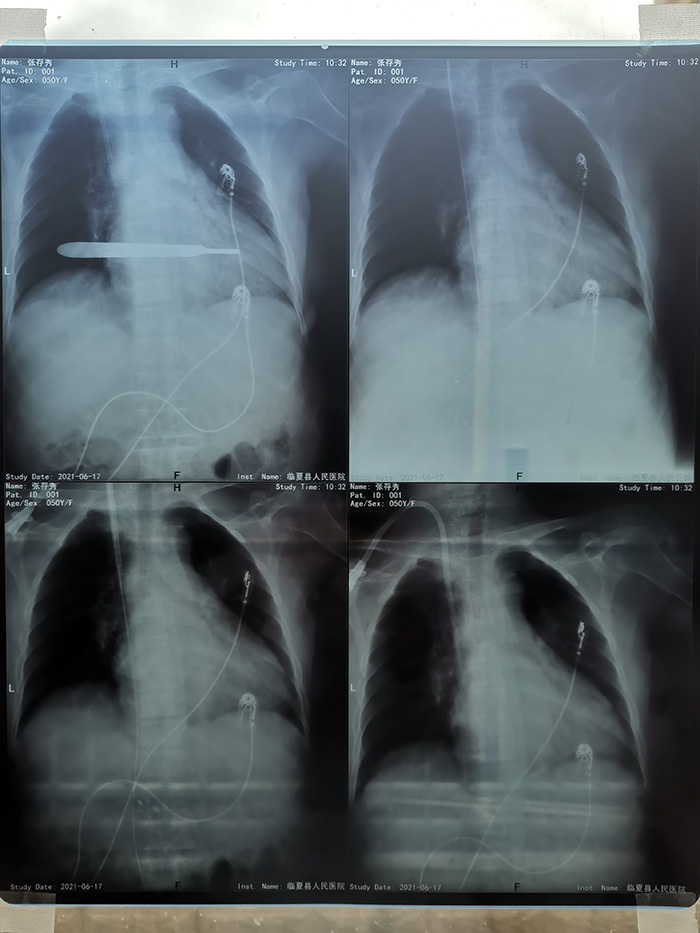

在临夏县人民医院马坚院长、陈明前书记、石灵成副院长等领导班子的大力支持下,临夏县人民医院肾病科与放射科制定周密的手术方案,在X线机引导下为1例尿毒症患者成功置入第三代长期血液透析导管,同时实现了长期血液透析通路建立的日间手术模式,术后患者步行离开术间,在血液透析室留观并进餐后返回。临夏县人民医院肾病科王丽娟护士长和陕学梅护士长参与术后留观、导管护理等工作,并向患者及家属详细交代术后注意事项,为患者围术期的加速康复探索了新的护理模式。

相较于传统的一代和二代导管,三代Palindrome导管头端为对称螺旋Z型设计,可以显著减少再循环率;采用单向阀撕脱鞘技术,预防术中空气栓塞和减少出血;采用Carbothane材料及激光切槽,具有优越的抗打折性能,并通过自我冲刷减少导管感染和纤维鞘形成率。X线机引导术中操作,可以确保导管头端放置位置更加精确,同时便于术中观察引导导丝及导管的整体走形。